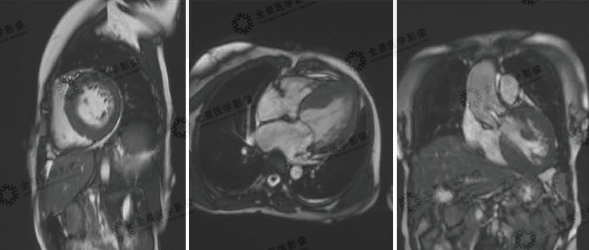

▲电影序列

全心变大,红色箭头:变薄心肌

▲心脏电影序列

心脏电影示心室壁运动无明显异常,各节段运动协调,LVEF:71.7%